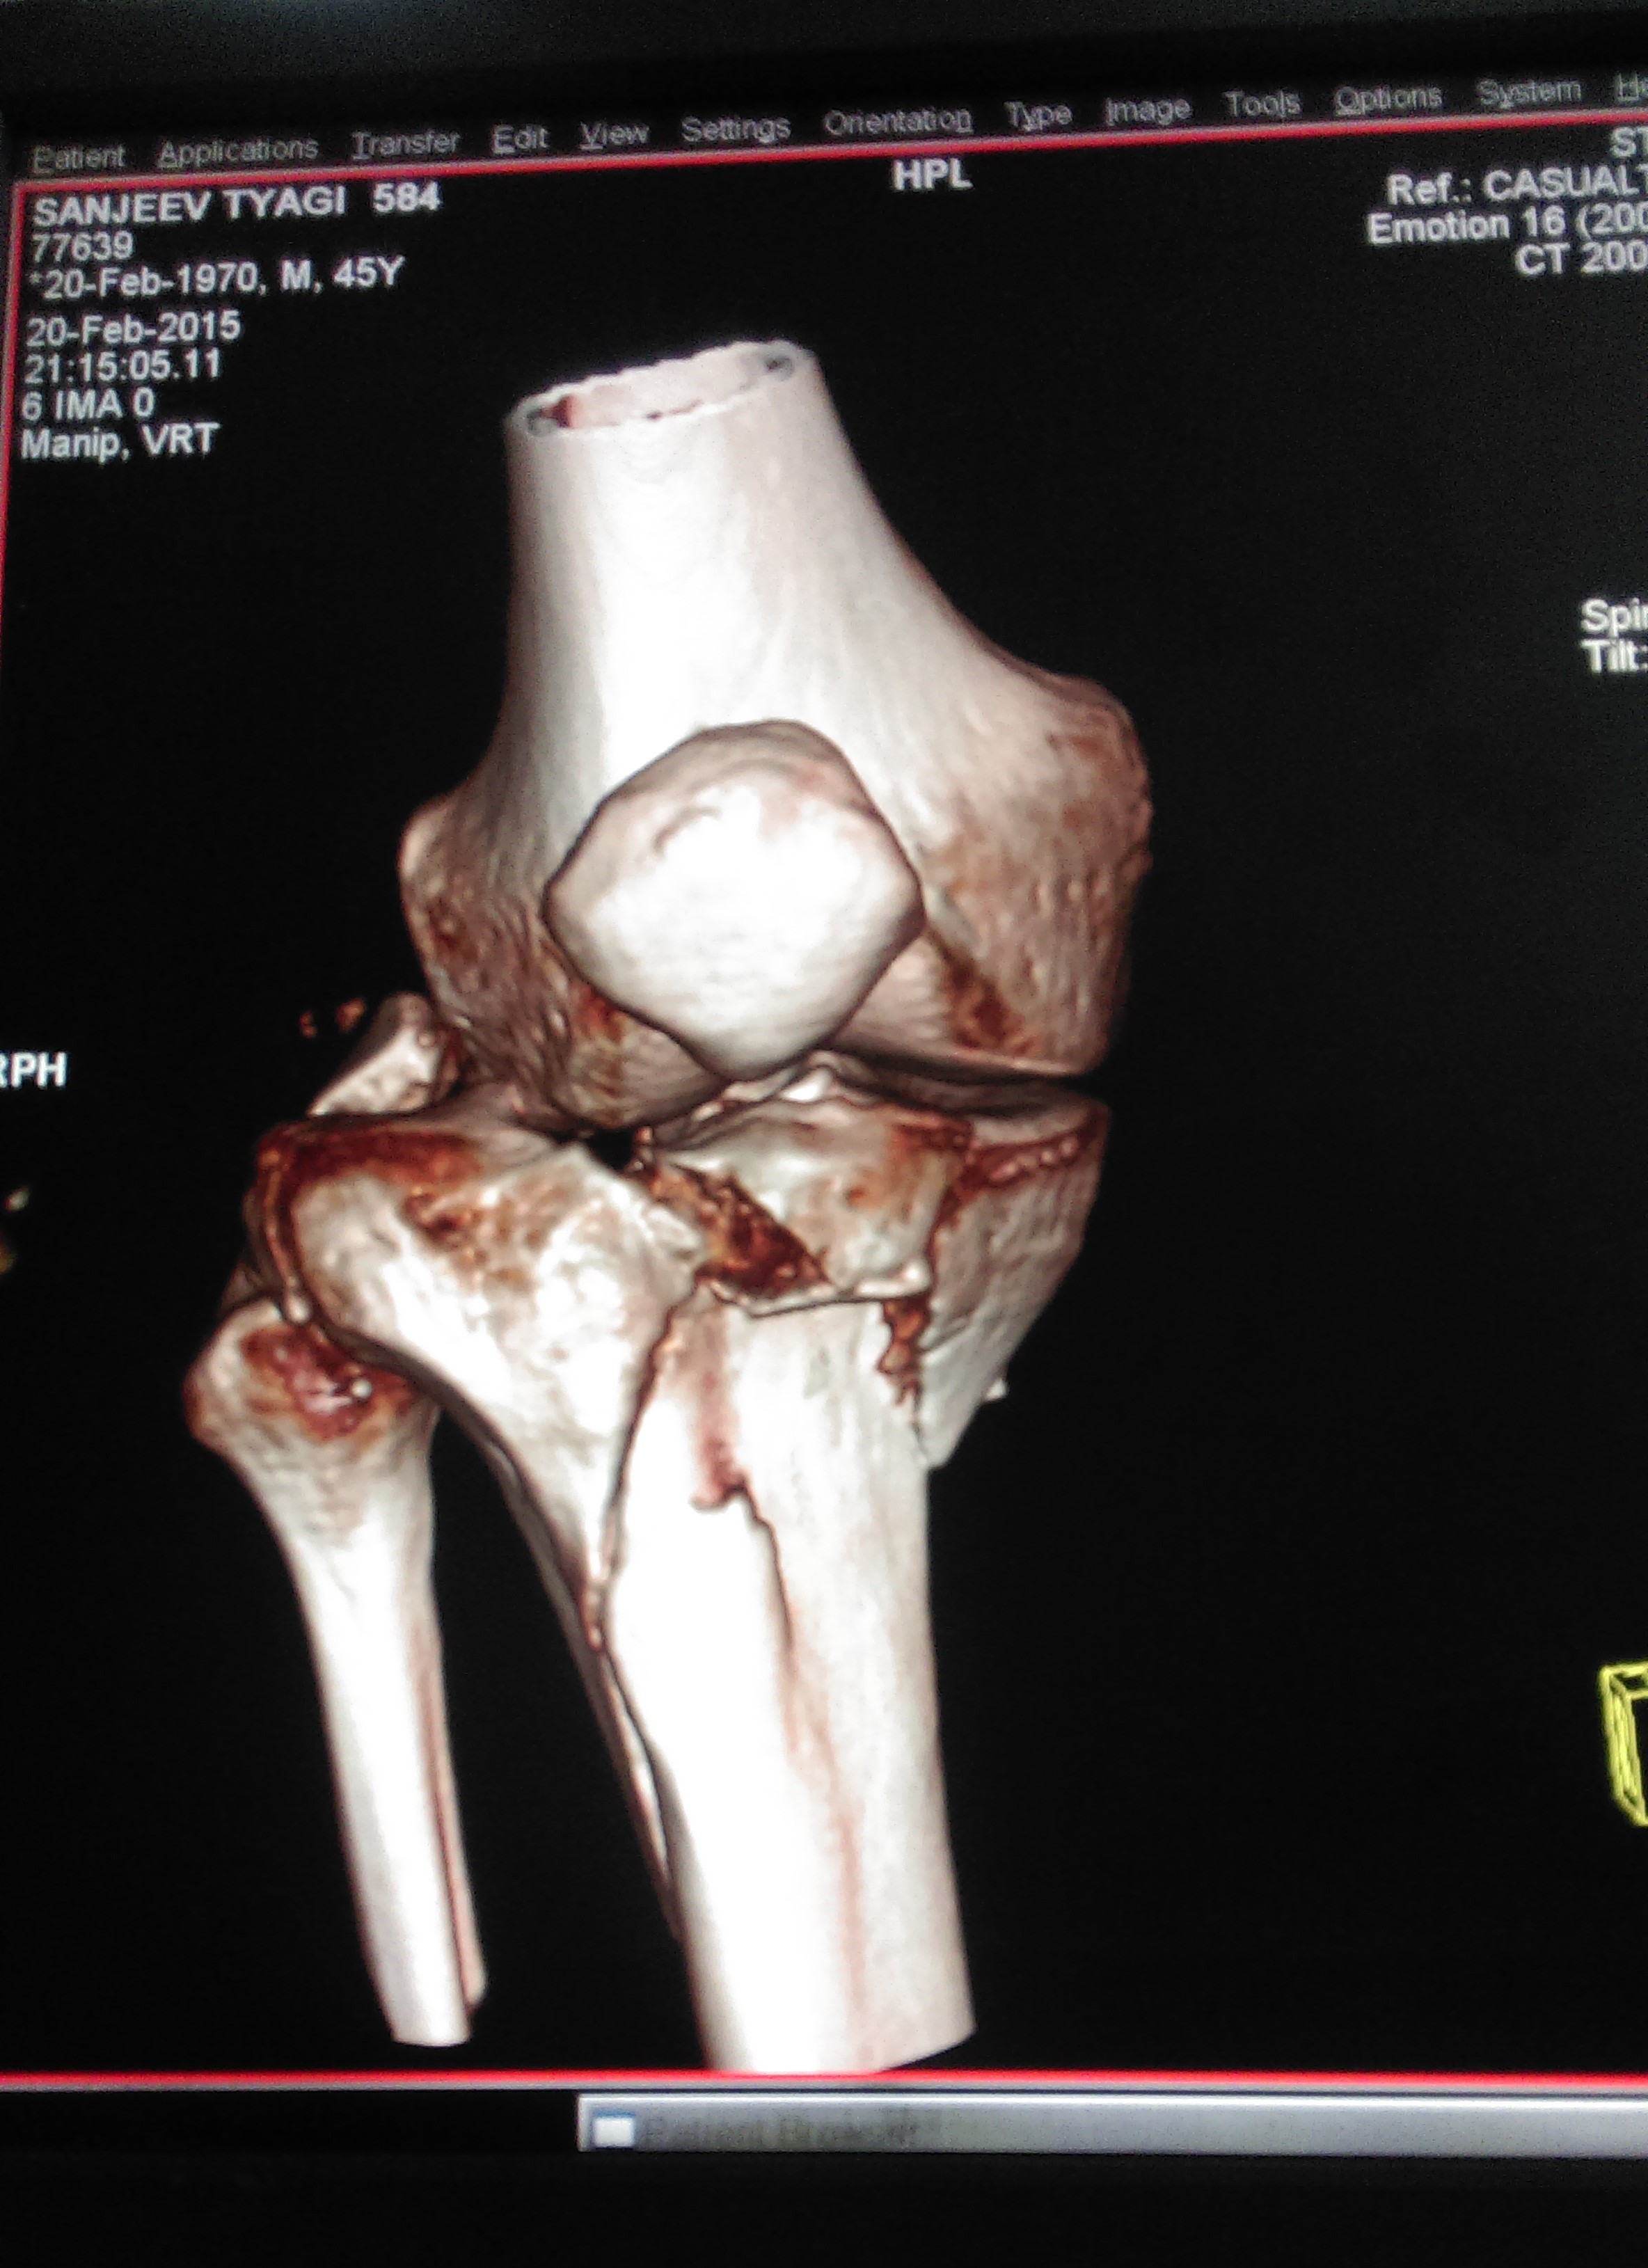

What is multi-ligament knee Injury?

Multiple ligament knee injuries happen when more than one of the knee’s ligaments is torn. They are less common than single ligament injuries.

What causes Multi-Ligament Knee Injury?

Multiple ligament knee injuries can occur during sports activities or through high-energy trauma, such as a fall from height or a car accident.

How Multi-ligament knee Injury diagnosed?

The most important way to initially diagnose these injuries is to review a thorough history with the patient to recall that their knee felt that it dislocated and slipped back in. It’s important to determine if this was solely their kneecap joint where there was a patellar (kneecap) dislocation or if it was the complete knee joint itself slipping out of place.

These injuries are very severe and potentially limb and life threatening. Thus, assessing for this and insuring that the patient’s knee function is intact, including both the status of the pulses to ensure that the artery is not injured as well as their sensation to ensure that there are no nerve injuries present is important.

How multi–Ligament Knee Injury Treated?

Nearly all cases of multiple ligament knee injury require surgery. The goal of surgery is to:

Restore knee stability

Regain full range of motion

Allow a return to athletic activities in the future

Before surgery, patients are prescribed physical therapy to work on regaining full motion and to decrease knee swelling. All patients wear a brace to protect the knee before surgery.